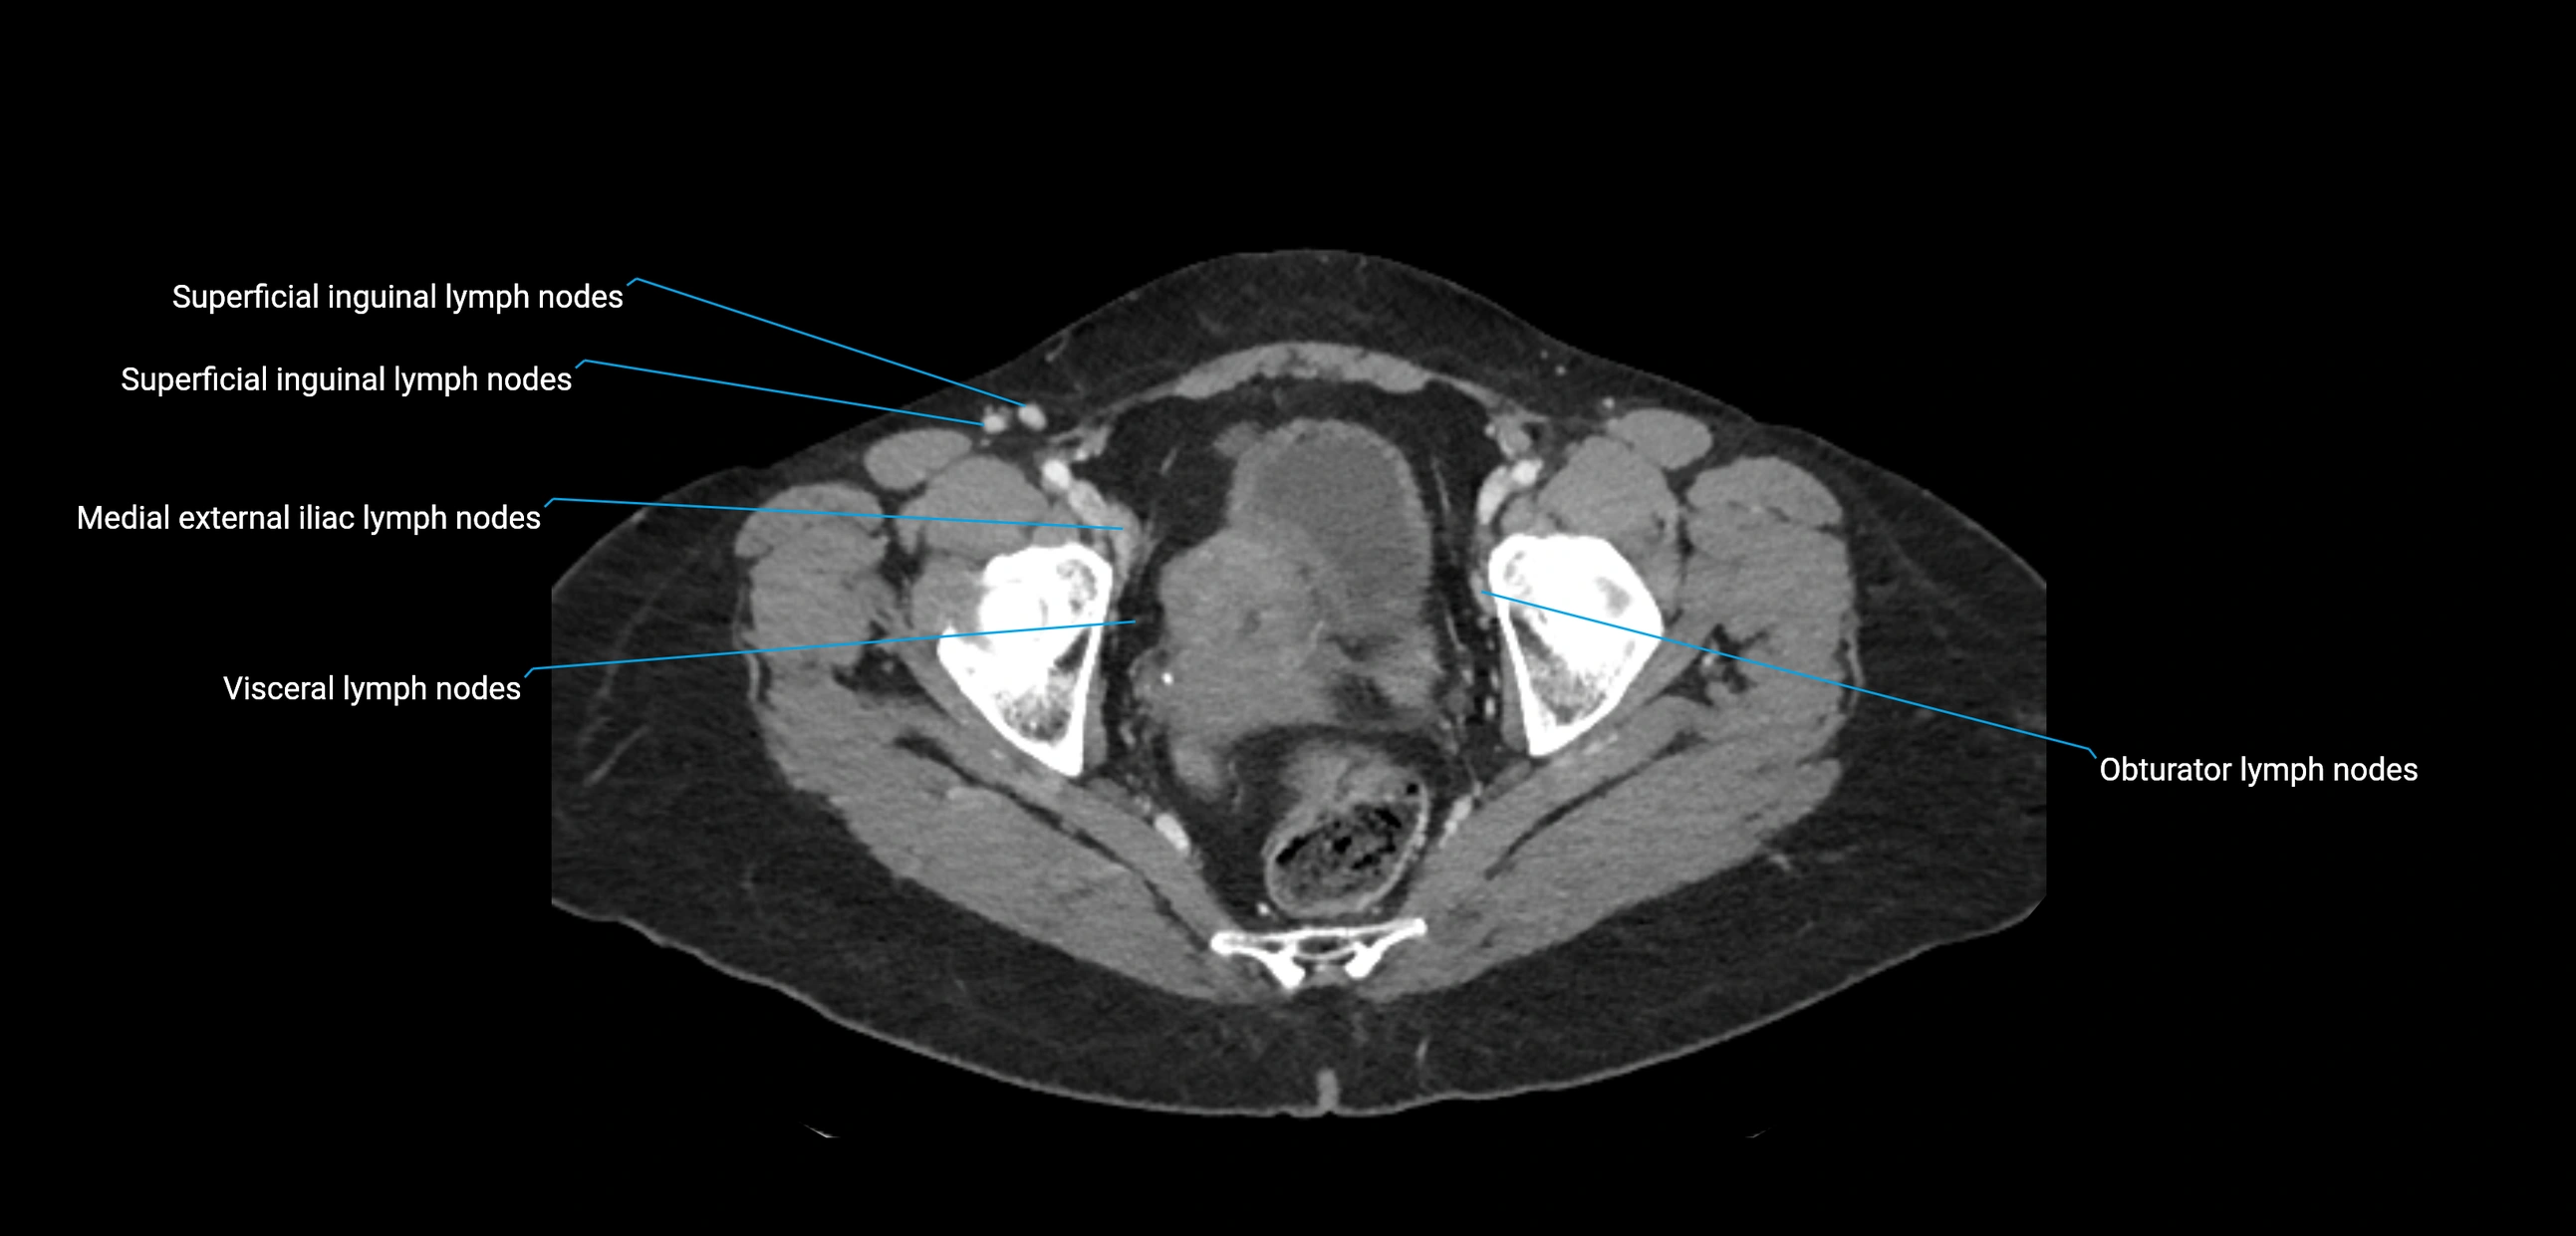

CT Appearance

CT Pre-Contrast:

• Nodes appear as soft-tissue density nodules adjacent to the aorta and IVC

CT Post-Contrast:

• Normal nodes enhance homogeneously

• Malignant nodes may show heterogeneous enhancement, central necrosis, or conglomerate formation

• Size >1 cm short axis is suspicious, though morphology and distribution are equally important

CT image

image